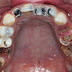

Nguyên nhân răng hàm bị sâu chỉ còn chân răng

Răng sâu chỉ còn chân răng là tình trạng sâu răng khá nặng. Nếu không có biện pháp điều trị sớm, sâu răng sẽ gây ra nhiều biến chứng ảnh hư...